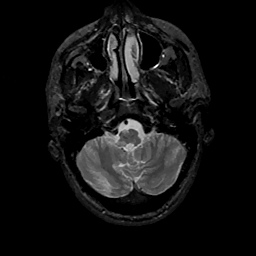

MR Study #11, May 5, 1991 -- Slice #8

[Home][Help][Clinical][Tour 1][Tour 2] Slice 8